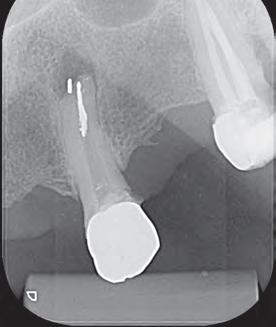

En la segunda sesión, 15 días después, realizamos la obturación convencional del tercio apical del canal con gutapercha, llenado de la cavidad reabsortiva con BIO-C ® REPAIR (Angelus, Londrina - Brasil) (Figura 7, 8 y 9), condensándolo contra las paredes con condensadores específicos y bolita de algodón humedecida y realizamos el sellado coronario con resina.

El BIO-C® REPAIR es un cemento reparador biocerámico listo para su uso. Se compone de silicato de calcio, aluminato de calcio, óxido de calcio, óxido de zirconio, óxido de hierro, dióxido

de silicio y agente de dispersión. El BIO-C® REPAIR presenta características superiores de adaptación marginal, biocompatibilidad, excelente radiopacidad y capacidad selladora en ambientes húmedos. Además de estas características, tiene como gran ventaja su facilidad de inserción a la cavidad reabsortiva

8 - Radiografia final

9 - Cavidad reabsortiva rellenada com BIO-C® REPAIR